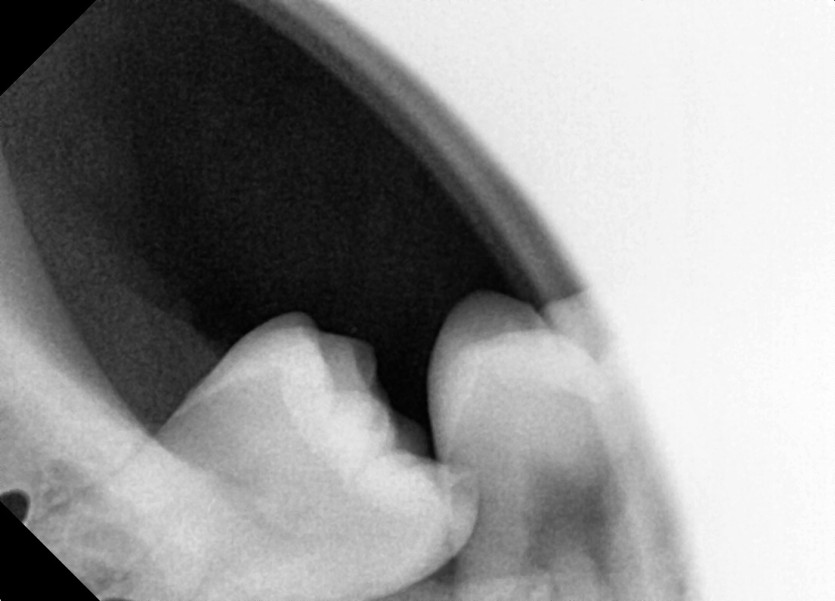

#18,48 사랑니 발치

구강 외과 전문의가 당일 발치했습니다.